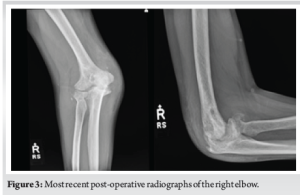

A 50-year-old right-hand dominant male presented to the orthopedic office for evaluation of chronic right elbow pain. He states this has been ongoing since he sustained an injury, while in the military, about 7 years ago. Over this period, he underwent 7 different surgeries related to this injury, with the most recent procedure in January of 2011. He noted considerable pain, stiffness, and significant difficulty performing tasks at work and activities of daily living. His pre-operative Visual Analog Scale (VAS) pain score was a 10 out of 10, mayo elbow performance score (MEPS) was 15/100 (<60 indicating poor performance), American shoulder and elbow surgeons (ASES) score of 18/100, and disabilities of the arm, shoulder and hand (DASH) score of 70/100 with additional noted severe difficulty performing his required work activities as a sports photographer. He also indicated that he was unable to participate in bowling, his sport of most importance, on pre-operative questionnaires. Radiographs and a computed tomography scan were obtained, which demonstrated advanced degenerative changes in the radiocapitellar and ulnohumeral joints (Fig. 1). Given his age, job requirements, and lifestyle, we felt the patient would not be a great candidate for a total elbow replacement given the activity and post-operative weight restrictions. Instead, we recommended treatment with an interpositional arthroplasty for the treatment of his post-traumatic osteoarthritis (Figs. 2 and 3).